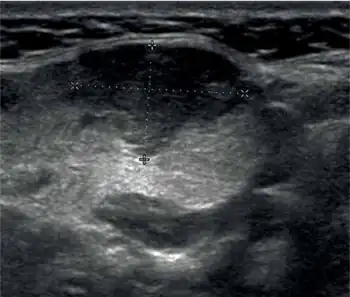

Given the difficulties of a definitive pre-operative diagnosis, the clinical entity of Küttner's tumor has so far remained significantly under-reported and under-recognized. In recent times, armed with a better understanding of the occurrences and observable features of this condition, surgeons are increasingly depending upon pre-operative ultrasonography along with Fine-needle aspiration cytological (FNAC) examinations to make an accurate presumptive diagnosis,[20] and according to one estimate, about 44% of patients undergoing submandibular resection are found to have this condition.[20] In the ultrasonogram, Küttner's tumor is characterized by a diffuse, heterogeneous zone of echo-shadows.[21] The FNAC finds cells greatly reduced in number (called 'paucicellularity') along with scattered tubular ducts against a backdrop of lymphoplasmacytic infiltration and fibrous depositions.[21] There may be a reduced but moderate number of cells and ducts enveloped in fibrous sheaths, as well as fibrous proliferation of the gland's septa.[22] The cytologic findings by themselves may not be specific, and the diagnosis requires adjunct consideration of both the ultrasonogram and clinical presentation. Application of magnetic resonance imaging (MRI) has been tried to non-invasively examine the morphological variations in Küttner's tumor and differentiate them from those seen in malignant tumors;[23] while MRI findings of the affected tissue and the pattern of cellular infiltration may offer some diagnostic clues for this condition, so far the results have been inconclusive.[23]